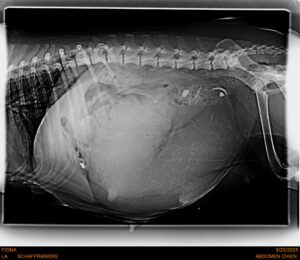

FIONA devrait venir à la suite, ce premier week-end d’octobre avec 7 chiots.

RADIO DE FIONA